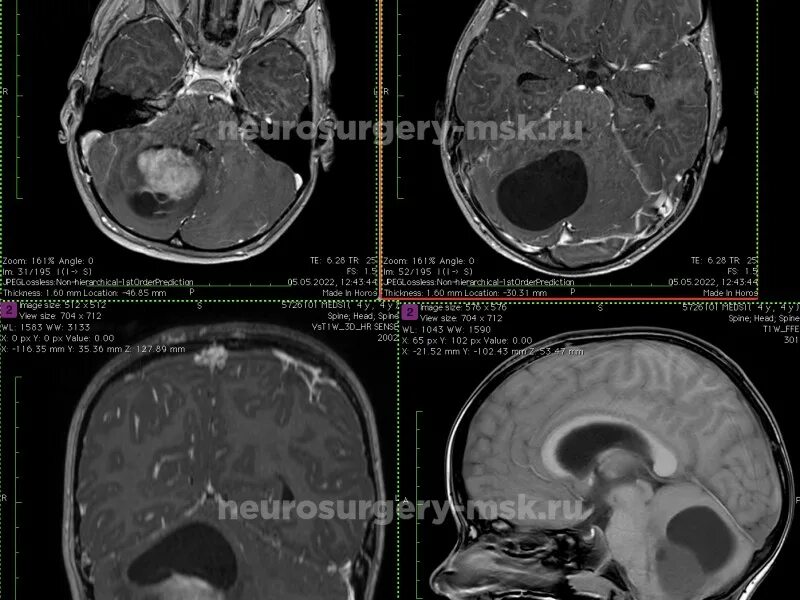

Астроцитома головного мозга прогноз после операции